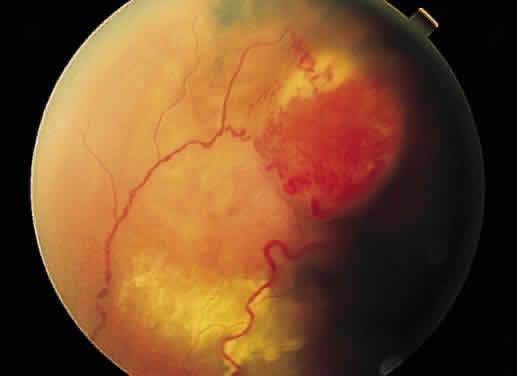

Fig. 25. Fundus photograph of cytomegalovirus retinitis with the classic admixture

of retinal infection (white) and hemorrhage, giving the so-called “pizza-pie” appearance. Fig. 25. Fundus photograph of cytomegalovirus retinitis with the classic admixture

of retinal infection (white) and hemorrhage, giving the so-called “pizza-pie” appearance.